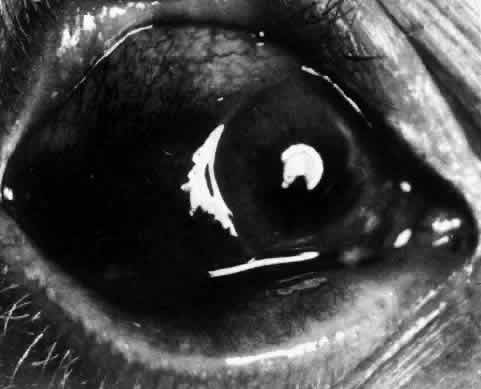

episcleritis and nodular episcleritis. ETIOLOGY Thirty percent of patients with episcleritis had some associated general conditions,6–8 but the rest defied all attempts to discover an etiology. Although some patients had a strong family history of atopy, results of patch and prick testing were uniformly negative. Of those in whom an etiology was found, only 5% showed any association with collagen disease, 7% had an association with herpes zoster, and 3% each had an association with gout or syphilis; the rest had associated conditions such as erythema nodosum, Schönlein-Henoch purpura, erythema multiforme, contact with industrial solvents, or penicillin sensitivity, indicating an immune basis for the condition. PATHOLOGY Microscopic and electron microscopic studies of biopsy specimens from patients with simple and nodular episcleritis have been totally noncontributory in the attempt to discover the etiology of this condition. The inflamed area is packed with lymphocytes and a few other inflammatory cells, but there are no mast cells, plasma cells, or eosinophils. CLINICAL MANIFESTATIONS The onset is usually acute; the eye may become red and painful in as short a time as half an hour. The patient's main complaint is redness of the eye, which is often sectorial and may be accompanied by a feeling of hotness, pricking, and mild discomfort. There is no discharge, although the eye waters occasionally. Pain may be absent, but the discomfort may be so severe that patients cannot pursue their normal occupation. The pain is localized to the eye, rarely radiating to the forehead and never producing the severe boring pain that is so commonly described in scleritis. In a severe attack the lids may become swollen, but this is a rare occurrence. If photophobia is present, an accompanying corneal condition should be suspected. Simple and nodular episcleritis differ in their clinical courses, but in both the edema and infiltration are entirely within the episcleral tissues. The sclera is not involved. The maximum congestion is in the superficial episcleral network, with some slight congestion of the conjunctival vessels and deep episcleral vessels (Fig. 10). The intraocular structures are not involved in either variety, nor is the visual acuity affected. Anterior segment fluorescein angiography reveals a normal vascular pattern but a very rapid flow rate, with the whole transit of the dye being completed within 2 or 3 seconds (Figs. 11 and 12).

The redness of simple episcleritis may be intense, varying from a fiery-red or a brick-red discoloration to a mild red flush, but it does not have the bluish tinge that is seen in scleritis. The distribution is usually sectorial but can involve the whole anterior segment of the globe. The episcleral vessels are engorged but retain their normal radial position and architecture (Figs. 13 and 14; Color Plate 1A). In simple episcleritis, there is a diffuse edema of the episcleral tissues. These tissues are sometimes infiltrated with gray deposits that appear yellow in red-free light. Surprisingly, the eye is rarely tender to the touch.